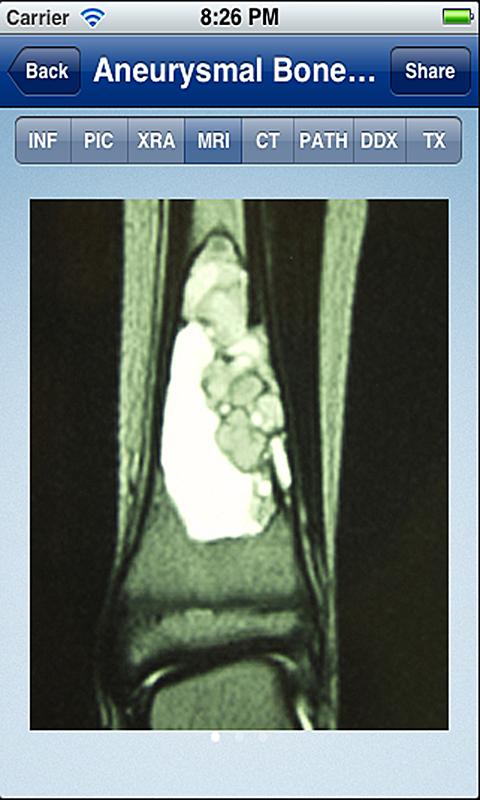

Cada aplicación Tumorpedia contiene información sobre 20 a 50 tumores diferentes, que abarcan la etiología, patogenia, presentación clínica y hallazgos de la exploración, así como la radiografía, resonancia magnética y tomografía computarizada de la aparición del tumor. Las características diagnósticas de cada tumor se ilustran con cientos de imágenes de ejemplos de casos reales. Además, los resultados de patología microscópicas se describen e ilustran. La aplicación ofrece opciones de tratamiento, información de los resultados y el pronóstico para cada tumor.